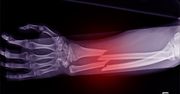

Złamania kości przedramienia